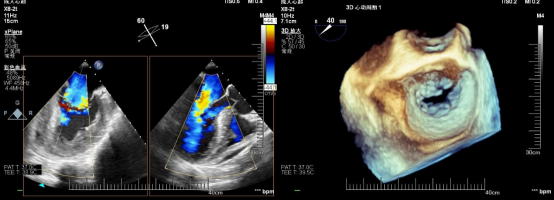

在患者全麻状态下经股静脉置管、经食道超声(TEE)引导房间隔穿刺后置入导引鞘管,手术团队将夹合器精准送达二尖瓣反流区。在TEE及X线引导下,手术团队利用二尖瓣夹(Mitraclip)准确捕获二尖瓣叶,试夹闭后经过超声证实夹闭有效,释放成型夹。术后超声评估,二尖瓣口仅见轻微反流,反流情况明显改善,患者各项生理指标正常,Mitraclip手术高质量完成。患者于术后第3天顺利出院,出院前检查患者二尖瓣反流各项参数指标恢复都超出了预期效果。

术后心超